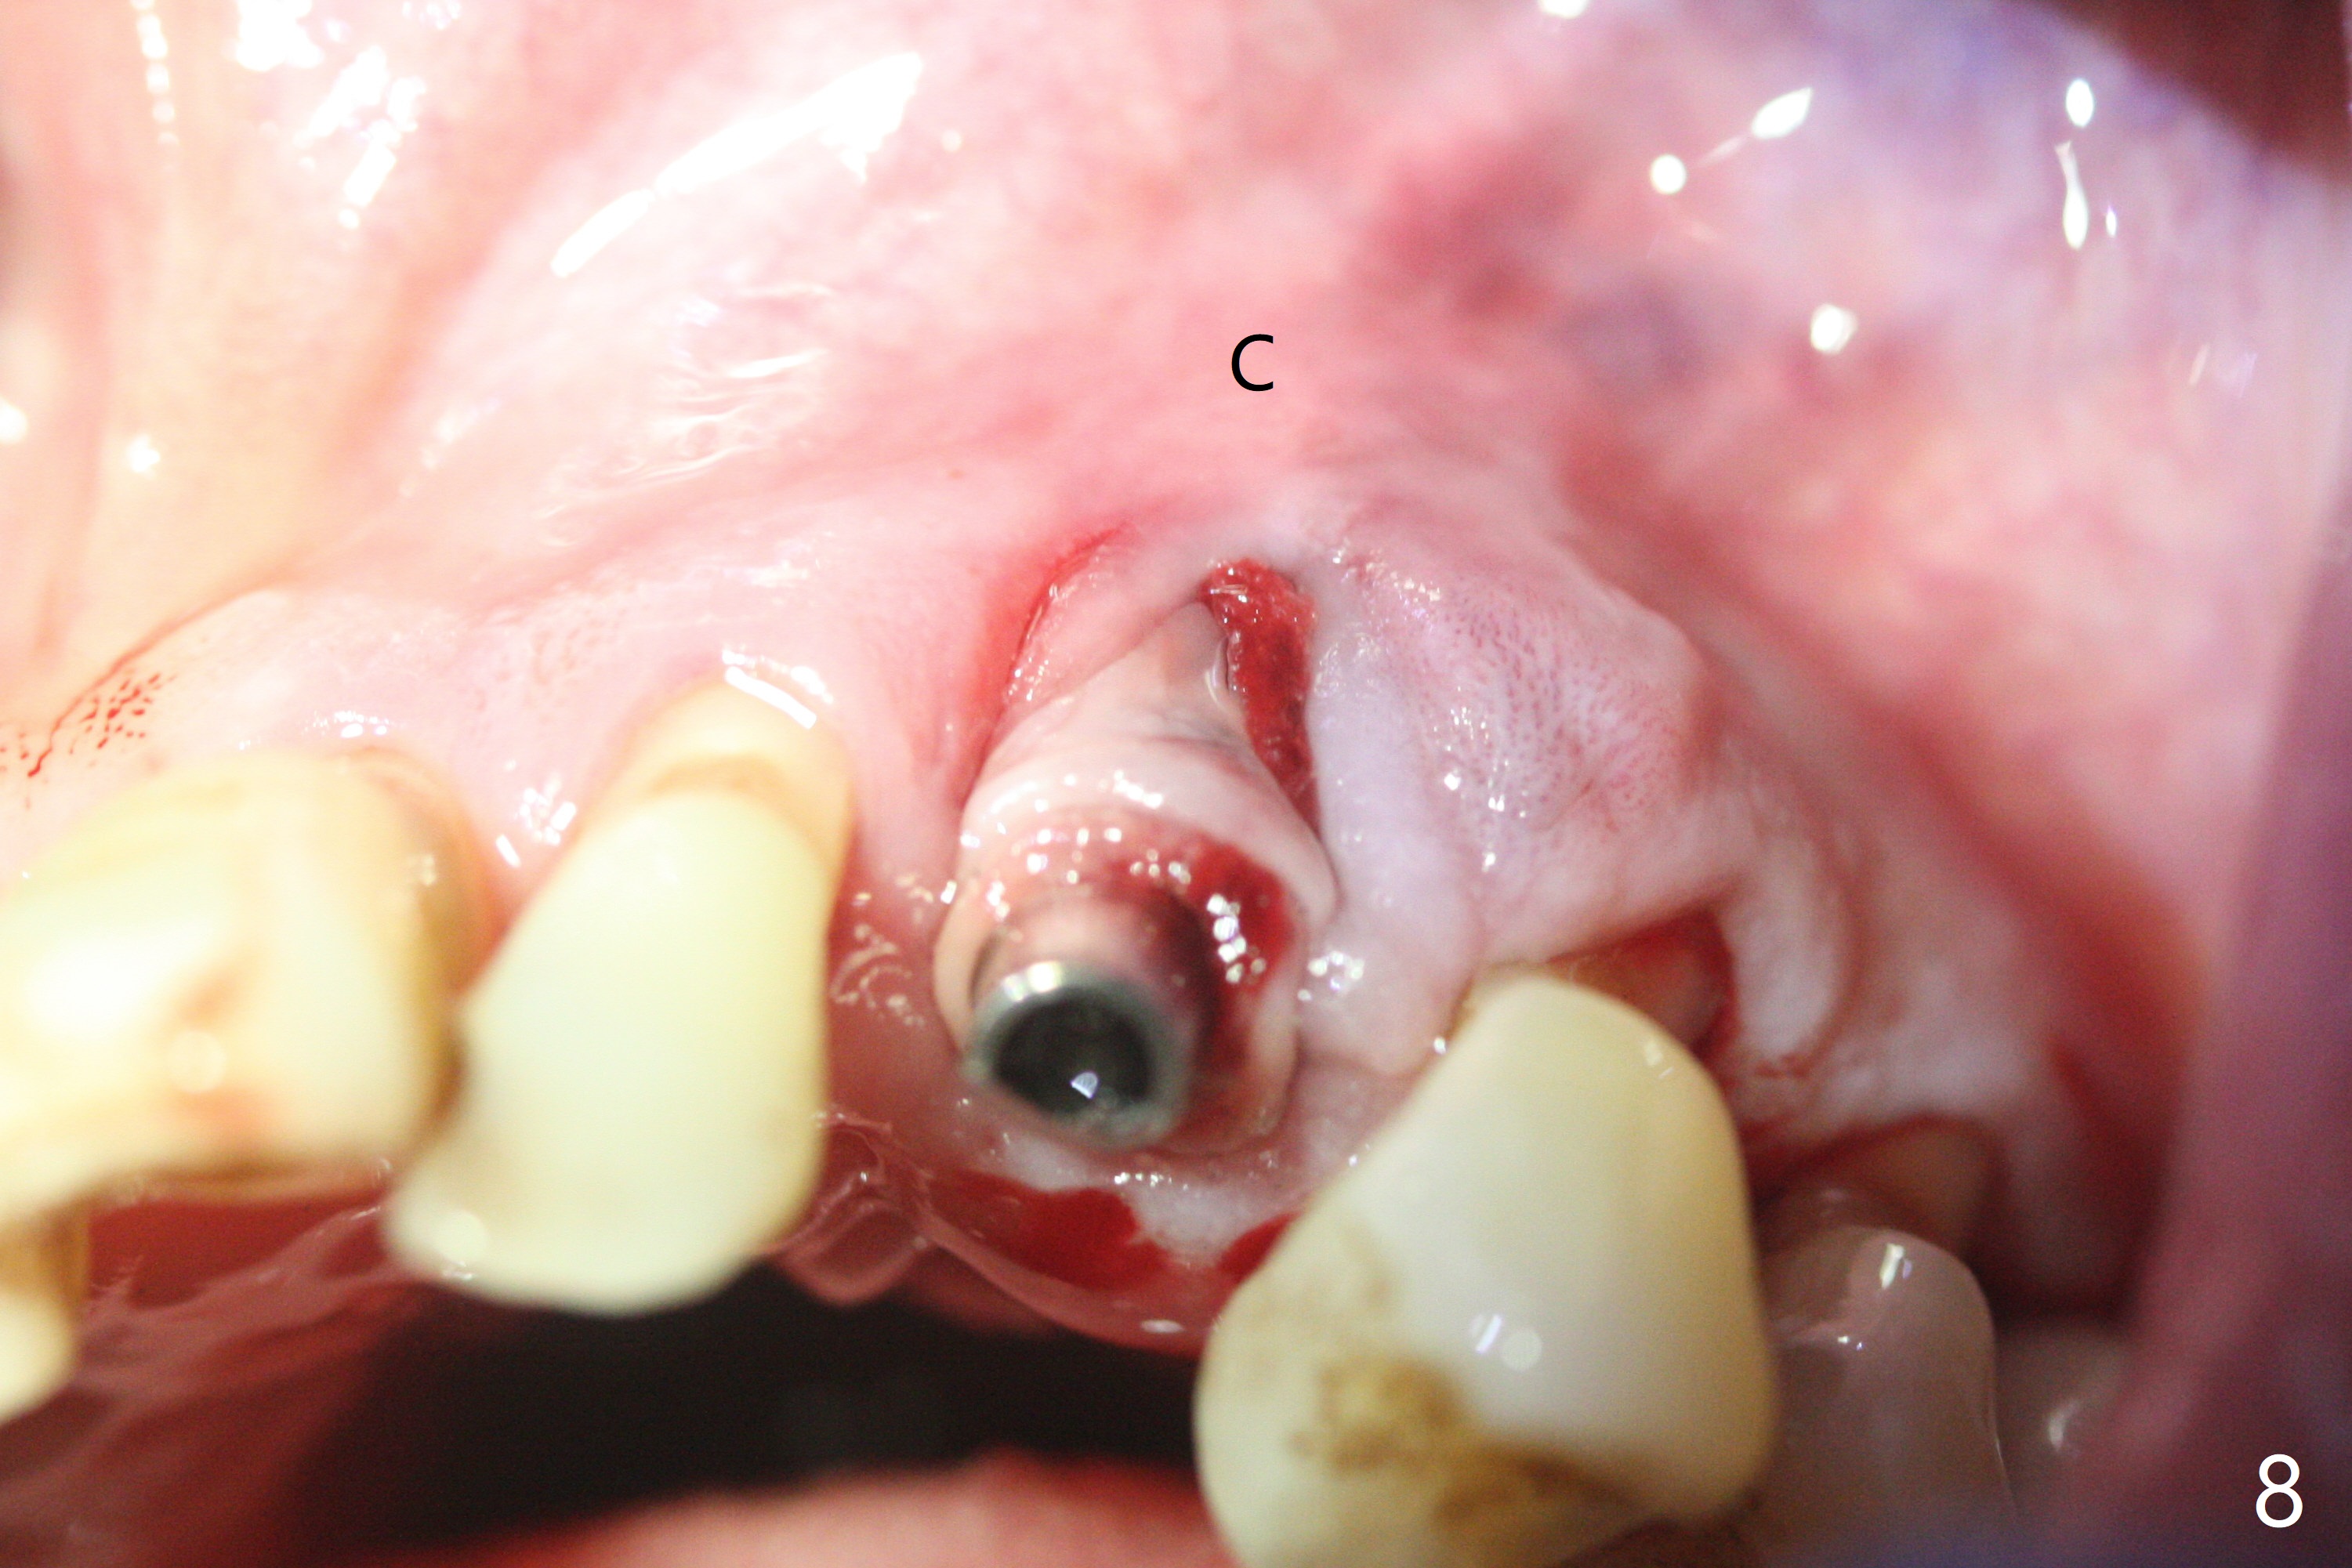

A 62-year-old man with generalized chronic periodontitis returns with chief complaint of loose tooth at #11 (Fig.1). Although a buccal fistula (Fig.1 <) is closer to #12 than to #11, percussion is more severe at #11 than 12. The buccal plate of #11 is missing, but it is possible to place a narrow immediate implant because of the wide alveolus (Fig.2). Since the gingiva is ~ 10 mm long, a mill abutment is to be used (Fig.3,5). In fact the fistula communicates with #11 extraction socket. After debridement, osteotomy is initiated (Fig.4) for a 3.8x10 mm implant ~ 35 Ncm, followed by seating a 4.5x2 mm mill abutment (Fig.5). Abundant sticky bone is placed in the remaining socket (for buccal plate reconstruction) and against the root surface of the neighboring teeth (Fig. 6 * (#10,12)). Finally 2 pieces of PRF membranes are utilized to facilitate repair of the buccal soft tissue defect (Fig.7 *). The root prominence of the canine seems to be maintained by the bone graft (Fig.8 C). Acrylic dressing holding the PRF membranes in place remains in situ with the healthy gingiva buccal (Fig.9) and palatal (Fig.10) 11 days postop. Note the acrylic locking into the undercuts of the neighboring teeth (*). 经过一段摸索发现离心每分钟1500转5分钟后,抽取上清液,接着再离心10分钟剩余上清液就形成血小板块,压制后便是血小板膜,后者似乎有助于软组织愈合,而上清液用来制备骨块,帮助硬组织生长。利用这个原则讨论以下病例治疗。The gingival margin gains ~ 5 mm 6 weeks postop when the acrylic dressing is removed (Fig.11,12 (<: previous one), as compared to Fig.7,8). 治疗结束时尖牙牙龈缘高于第一双尖牙(图七,八),六个星期后,尖牙牙龈缘却低于双尖牙(图十一,十二(箭头:原始牙龈缘))。术后2.5,4.5月基台周围牙龈似乎能与钛合金附着,防止细菌进入深部植体(图十三,十四)。临时牙冠脱落多次,可能与mill abutment太光滑有关,所以颊侧,舌侧磨成平面(图十四)。取模时好像不必取出基台清洗(仿佛没有炎症),原位用树脂延长基台。术后5个月CT显示颊侧骨板再生(图十六-十八)。取模时并没有用树脂加长基台;粘固时,牙冠颜色理想,但是照片中并不是如此(图十九,二十),颊侧骨板没有塌陷。术后11个月基台颊侧骨板没有萎缩(图二十一:B);3d图像:骨壁完全形成(图十六对比:部分形成)。密度也增高(图二十二:B),与术后五个月比较(图十七)。术后十一个月,粘固后五个月角化龈存在(图二十三),牙冠颈部有金属颜色透出,是因为二段式基台太粗了(最细4.5毫米),可以请实验室在牙冠内部涂opaque material而减轻。